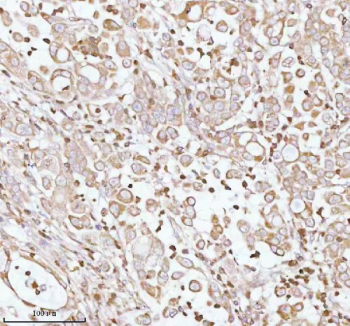

Immunohistochemical staining of PLBD2 using anti-PLBD2 antibody. PLBD2 was detected in a paraffin-embedded section of human lung adenocarcinoma tissue. Heat mediated antigen retrieval was performed in EDTA buffer (pH 8.0, epitope retrieval solution). The tissue section was blocked with 10% goat serum. The tissue section was then incubated with 2 ug/ml rabbit anti-PLBD2 antibody overnight at 4oC. Peroxidase Conjugated Goat Anti-rabbit IgG was used as secondary antibody and incubated for 30 minutes at 37oC. The tissue section was developed using an HRP secondary and DAB substrate.